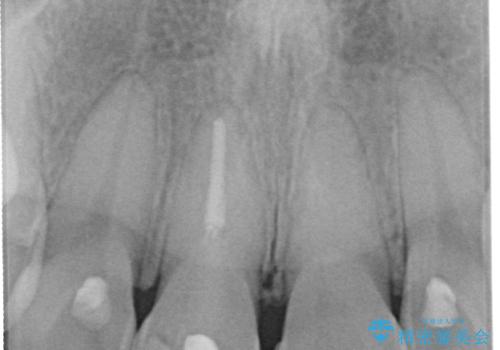

- 神経を取り除いた後に歯の色が変色して気になってきたとのことで来院された患者様です。

前歯は片側のみ神経を取り除かれていましたが、反対側もむし歯治療の詰め物が広範囲に及んでいたため、両方の歯をオールセラミッククラウンにて補綴治療を行うこととしました。

奥歯も著しく茶色に変色していたため、同様にオールセラミッククラウンにて補綴治療を行うこととしました。